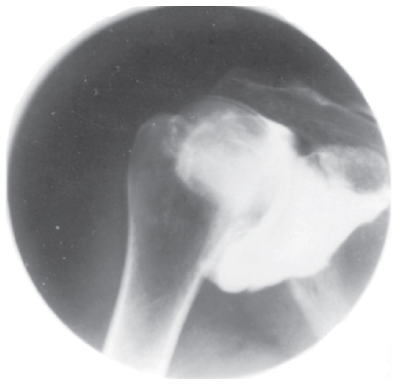

Shoulder arthrography is performed to

C - 2 and 3 only

Shoulder arthrograms (Figure 2–64) are used to evaluate rotator cuff tear, glenoid labrum (a ring of fibrocartilaginous tissue around the glenoid fossa), and frozen shoulder. Routine radiographs demonstrate arthritis, and the addition of a transthoracic humerus or scapular Y projection would be used to demonstrate luxation (dislocation).